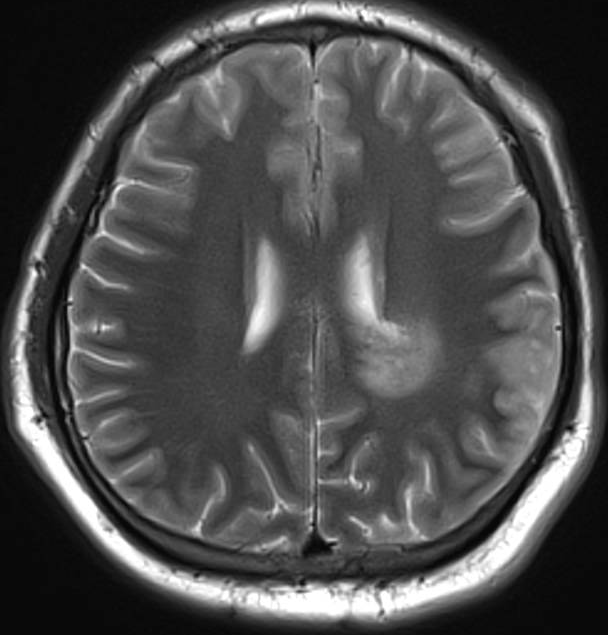

医生要求紧急做颅脑MRI,影像很快就传到了电脑上(图1-6)。医生解释,小脑蚓部占位考虑“脂肪瘤”,另有侧脑室旁白质脱髓鞘和左侧额顶叶皮质性脑炎的改变,“癫痫”可能为“继发性癫痫”。

图5 侧脑室旁病变T2

图6 侧脑室旁病变T2压水压脂